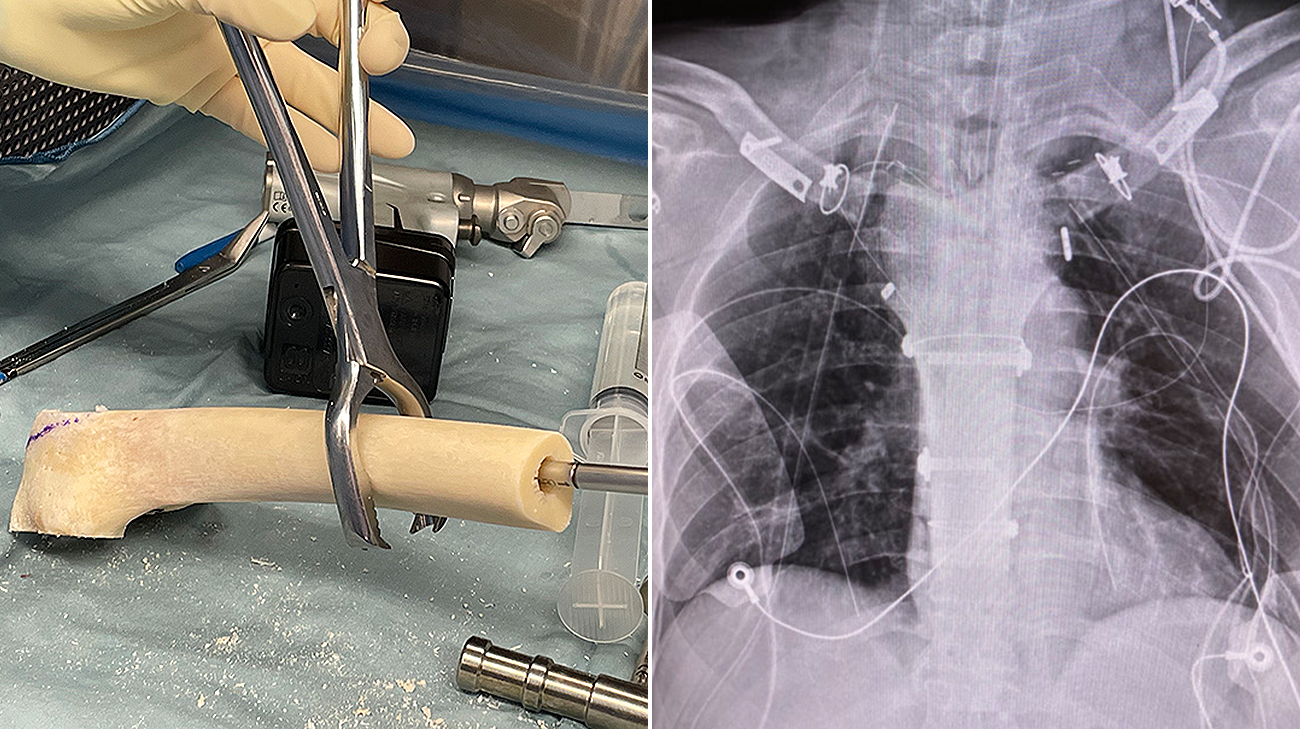

A femoral allograft was obtained from a national bone bank and prepared to fit the sternal defect.(left) A chest X-ray shows the final sternal reconstruction.(right) (Courtesy: Cleveland Clinic)

To address Edward’s tumor, most of the sternum as well as both sternoclavicular joints (the only skeletal attachment between the arms and axial skeleton) needed to be removed and rebuilt. Removing the sternum and sternoclavicular joints is so rare there is no established standard of care, and artificial implants do not exist. Drs. Raymond and Mesko worked together to create a solution that involved using a cadaveric femur in place of a sternum. During the procedure, the femur would be suspended from both clavicles using a synthetic aortograft (a flexible but tough polyethylene tube used to treat aortic aneurysms), a polyethylene terephthalate suture and a polyethylene cord used for ankle stabilization.